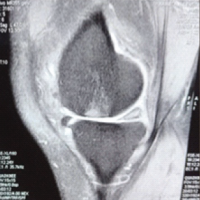

Ethical approval was obtained from the institutional review board. Patients aged 18–60 years with clinical and radiological evidence of MLKI (defined as injury to two or more ligaments, including the ACL, PCL, MCL, LCL or posterolateral corner (PLC) were included. Exclusion criteria were open knee injuries, isolated meniscal tears without ligament injury, or patients unwilling to consent. Pre-operative assessment included detailed history taking, physical examination using standard tests (Lachman, anterior/posterior drawer, varus/valgus stress, dial test), magnetic resonance imaging (MRI), and stress radiographs. Surgery was planned based on clinical findings and confirmed by MRI. All patients underwent arthroscopic or combined open-assisted single-stage reconstruction, depending on the structures involved. ACL and PCL reconstructions were done arthroscopically. MCL or PLC injuries requiring surgical management were addressed using open techniques. Grafts used included ipsilateral semitendinosus-gracilis (STG) autografts or peroneus longus (PL) autografts when hamstring quality was poor. Graft fixation methods included suspensory (cortical button) and aperture (interference screw) devices. Post-operatively, patients were placed in hinged knee braces. Weight-bearing was allowed as tolerated from day 2 with the brace locked in extension. Gradual range-of-motion exercises began within the 1st week after surgery. Standardized rehabilitation protocols were followed.

MLKIs are relatively rare injuries but clinically significant due to their complexity, potential for long-term instability, and high functional demands from an often young, active patient population. The incidence in our series mirrors recent epidemiological data from Westermann et al. [1] and Lindsey et al. [3], with young adult males predominating and RTAs accounting for the majority of cases. This injury pattern is particularly relevant in low- and middle-income countries (LMICs), where the increasing use of high-speed vehicles has been associated with a rise in MLKI incidence [23]. Public health interventions, including road safety campaigns and the adoption of protective sports equipment, remain crucial in preventing these serious knee injuries. Accurate diagnosis of MLKIs requires a combination of thorough clinical evaluation and imaging. While MRI is an invaluable tool, our data, similar to Al Mohammad et al. [2] and Fischenich et al. [12] – show that it may fail to identify certain ligament injuries, particularly in chronic or partially healed cases (Table 1). This underscores the continued importance of validated clinical tests, such as Lachman, posterior drawer, and dial tests. Scoping reviews [23] recommend that in resource-limited settings, clinical diagnosis should be prioritized when imaging is inconclusive or unavailable.